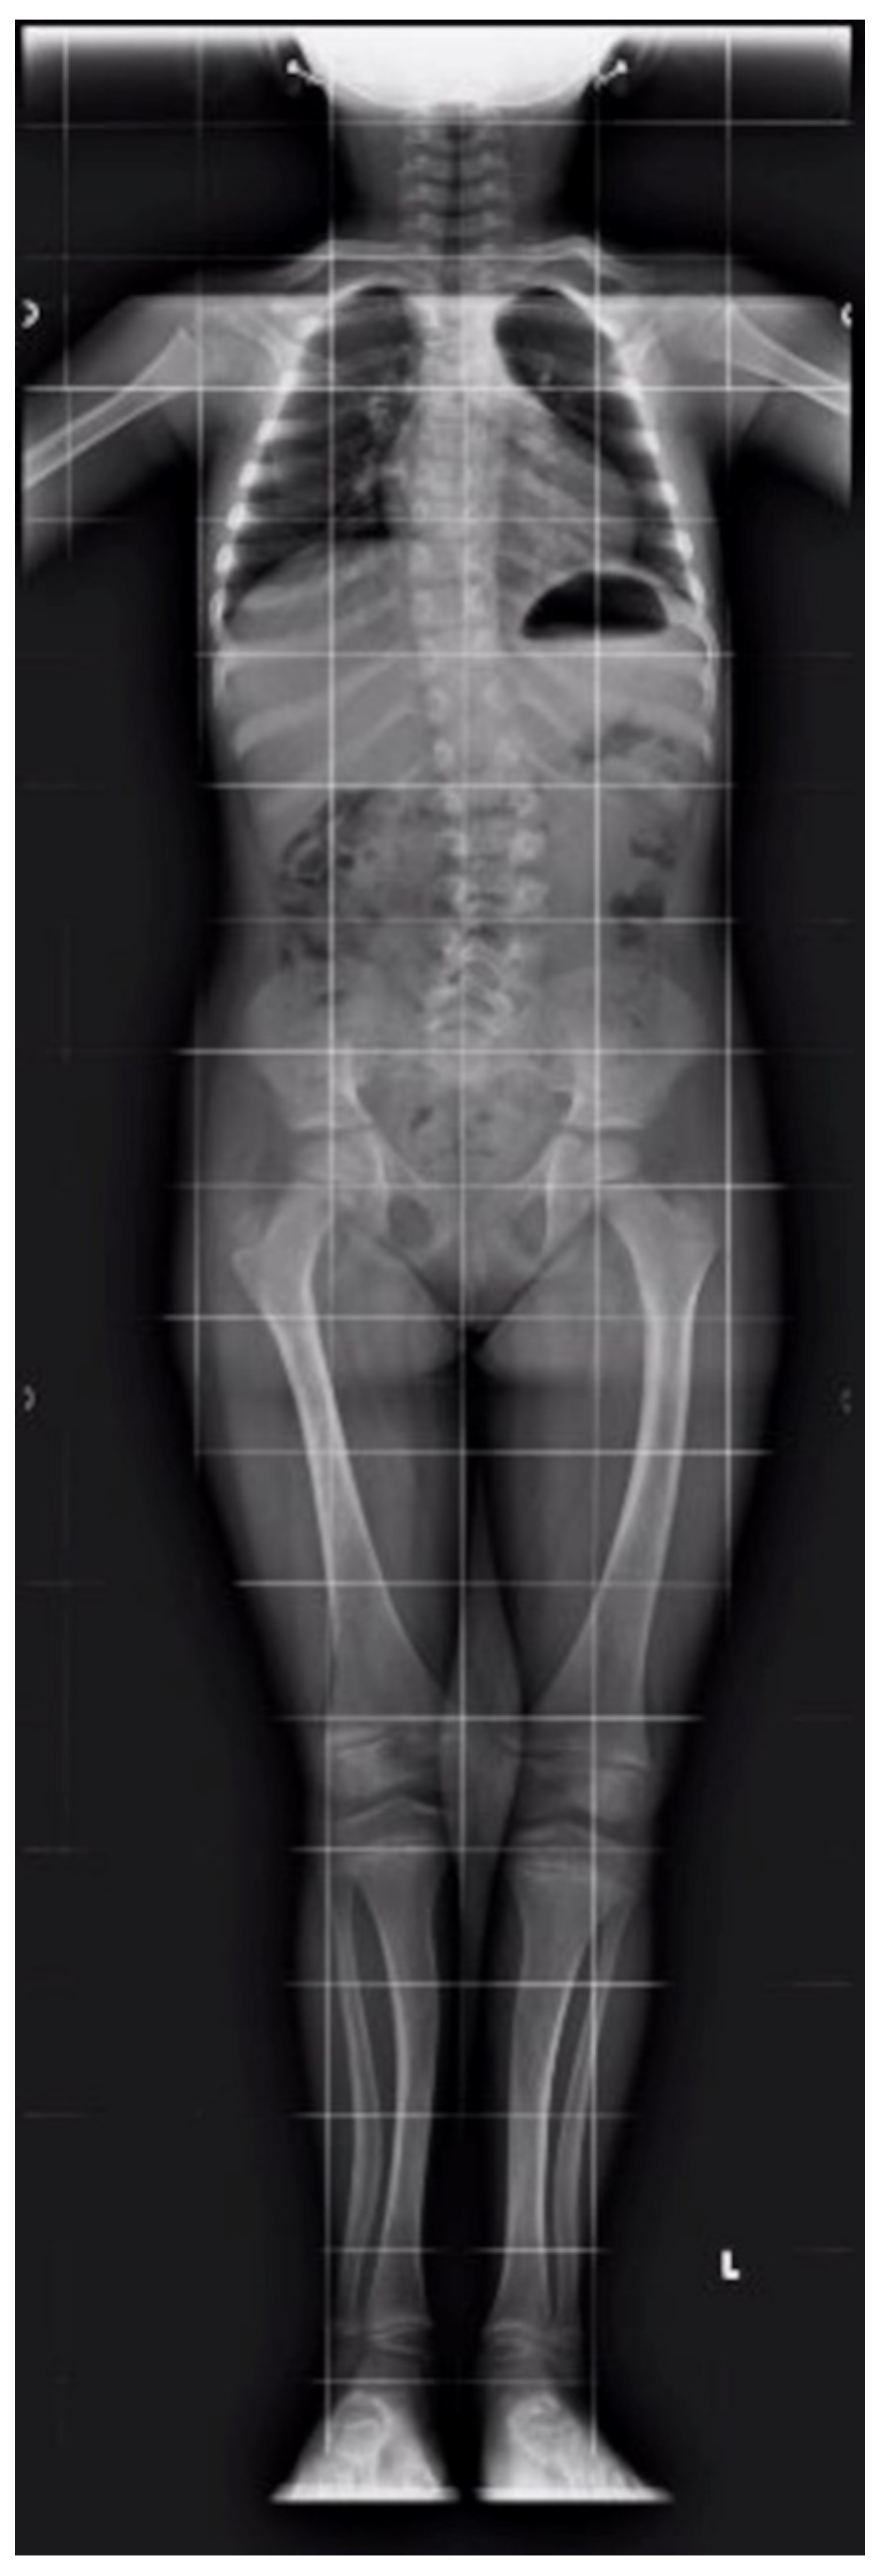

| Clinical features | Bone pain, osteomalacia ankle soreness, low back pain, fatigue, pseudofractures | Rachitic lesions at the wrists and knees, growth retardation | Genu valgum, decreased energy, moderately severe rickets | Rachitic rosary, metaphyseal widening, fraying and cupping of the ulna and the distal femur | Genu varum, growth retardation | Bone deformities, dental hypoplasia, frontal bossing, short stature, pectus carinatum, anterior bowing of both legs, pelvis retroversion | Bone deformities, dental hypoplasia, frontal bossing, short stature, pectus carinatum, anterior bowing of both legs | Genu varu, severe rickets, waddling gait | Rickets, short stature, pain in spine/hips/legs and difficulty in walking, kyphoscoliosis, proximal muscle weakness in all four limbs, and genu varus, deformity of bilateral lower limbs | None | Hypotonia, Rickets, growth retardation |

| Treatment | Vitamin D 50.000–100.000 U/day | Vitamin D 25.000–50.000 U/day, then vitamin D 5–25.000 U/day (vitamin toxicity) | Vitamin D 30.000–50.000 U/day At 11 ys calcitriol 0.25–0.5 mcg twice daily | Calcitriol 0.125 mcg/day Oral phosphate 220–400 mg/day | Oral phosphate + Calcitriol (doses not available) | Oral phosphate (doses not available) | Oral phosphate (doses not available) | Oral phosphate 64 mg/kg/day Alfacalcidol 20 ng/kg/day At 8 ys iron sulfate solution | Vitamin D and calcium till 5 y of age. Since age of 13: Phosphate 60 mg/kg/d in four divided doses and calcitriol 60 ng/kg/d in three divided doses for 6 months | NA | Oral alfacalcidol (0.020 mcg/kg/day) and oral phosphate (30 mg/kg/day, divided in 3 doses) |

| Symptoms Resolution | No | Yes | Yes | Yes | Yes | Yes | Yes | Yes | Yes | NA | Yes |

| Age at last follow-up visit (H/W if available) | 22 ys H: 163.1 cm W: 65.9 kg | 20 ys | 19.75 ys H 178.8 cm | 8 ys | 3 ys 6 mo | 9 ys H: 138 cm | 12 ys H: 150 cm | 11.5 y H: 125.3 cm (−3.23 SDS) W: 26.2 kg (−2.2 SDS) | 13 y | NA | On going |